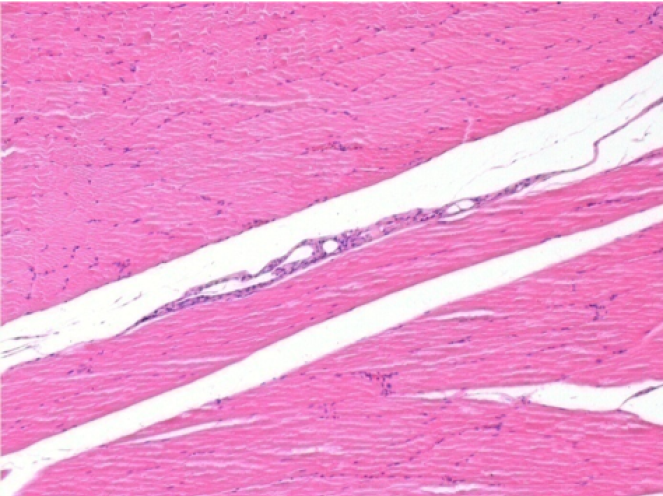

3 months (D90)after Endopeel Injection 0.1ml in the right pretibial muscle.